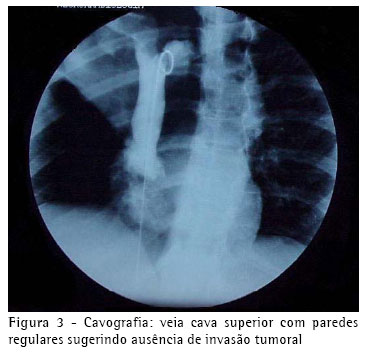

A tomografia computadorizada de tórax mostrava uma atelectasia do lobo superior direito por broncoestenose oclusiva do brônquio lobar superior, que se estendia até a porção justacarinal do brônquio principal, acompanhada de infiltração, inclusive da parede do brônquio principal esquerdo, e determinava invasão do ramo direito da artéria pulmonar e do cajado da veia ázigos. Não havia sinal de invasão da parede torácica, nem de derrame pleural (Figura 2).